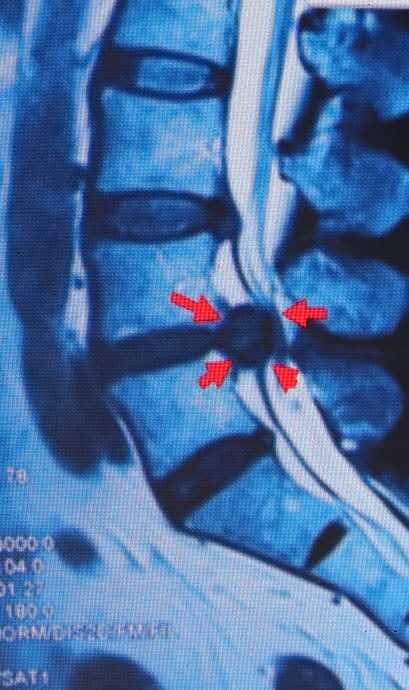

超声下引导体横下韧带针刀松解方法:固定好超声探头,穿刺点处给予0.5%利多卡因进行局部麻醉。用汉章牌3号1.0规格针刀(1.0mm×80mm),刀口与身体长轴平行,采用平面内穿刺,外侧入路,在超声实时引导下刺入皮下,缓慢深入,观察针尖准确触及横突上缘呈中强回声的窄薄层区,此时可感到针下为纤维样坚韧组织。

继续缓慢进针穿过该组织后,可感到针下触及坚硬骨质。在此区域由外上向内下纵向铲切,针下触及骨质后略退针并重复上述铲切操作(约4-5次),幅度不超过3mm,铲切全程必须保证可明确观察到针尖位置。操作过程中如果患者有触电感、剧烈疼痛等不适时,立即停止进针、松解等操作。

针下有松动感后即可出针,出针后可见目标区域回声强度减弱。针孔部按压3分钟,以无菌敷料贴敷穿刺点,治疗结束。嘱患者平卧休息30分钟。